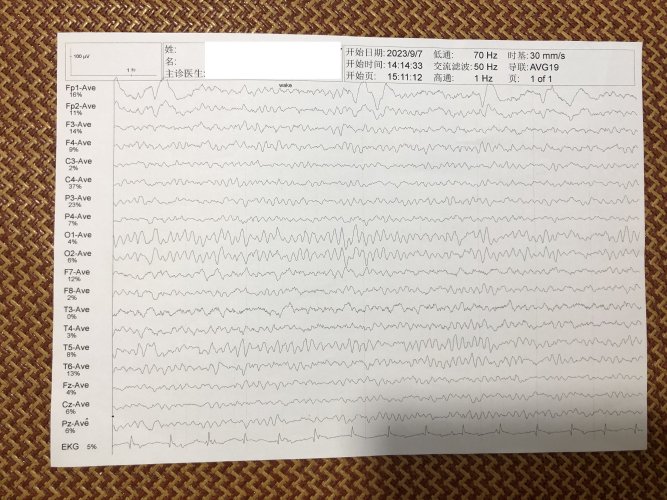

反馈下情况,孩子在国内的医院已经进行过一轮全面检测,没发现什么问题,但是现象是存在的。医生也没什么办法。医生说核磁共振和脑电图没问题,我们也不是很看得懂,各位如果懂的,请指点一下。另外进行了部分基因检测,没发现异常。下一步,我们国庆后打算去更权威的医院去碰碰运气。谢谢各位!

513.6 KB 查看: 103

532.8 KB 查看: 142

551 KB 查看: 132

526.8 KB 查看: 133

510 KB 查看: 103

506.4 KB 查看: 124

495.7 KB 查看: 165

435.1 KB 查看: 151